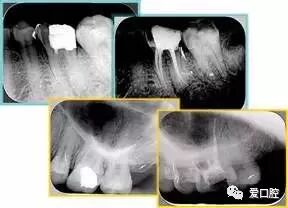

六、根管充填

充填时机,无自觉症状,无明显叩疼,根管内无异味,无渗出,无急性尖周炎症状即可充填,不必等到所有症状消失,反复的封药容易对尖周造成大大刺激。充填的方法,质控标准:

a、充填物距根尖小于等于2mm。

b、充填致密,连续,锥度合适。

c、充填完毕烫牙胶尖根管口下2~3mm,小号充填器冷加压。

d、对于欠充患者需重新预备充填,而超充原则上不建议重做,随访,必要时根尖手术治疗。目前研究表明,在其他因素相同的前提下,超充的预后差于欠充。